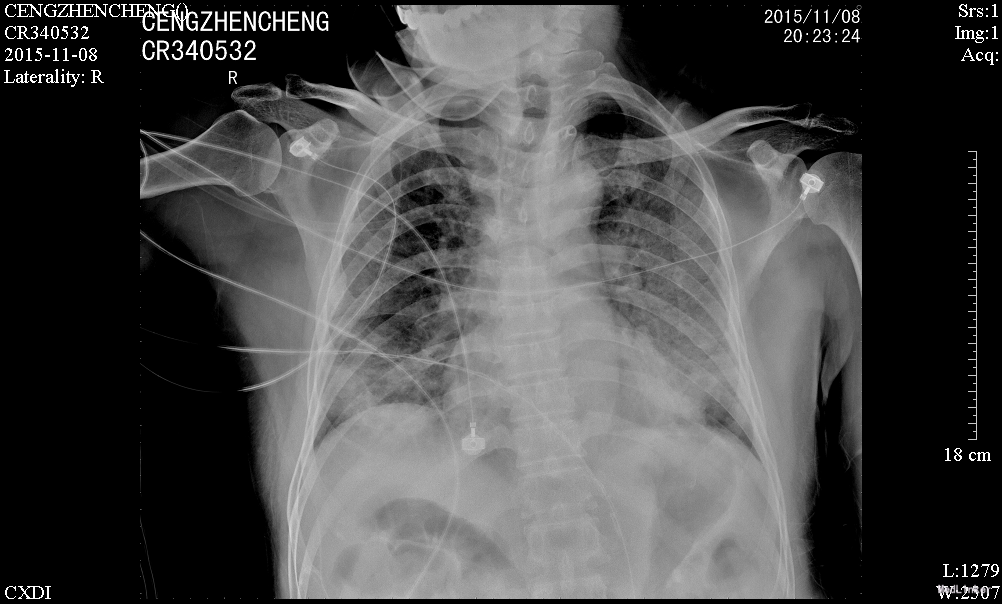

患者诉仍有咳嗽咳痰、呼吸困难、胸闷气促,咳白色粘痰,平卧及活动时加重,坐起后缓解,无发热,无咯血,精神、睡眠一般,饮食欠佳,大小便正常。高流量吸氧(7L/min)下血氧饱和度维持在93-95%,心率65-75次/分。查体:神志清楚,查体合作,胸廓未见异常;双肺呼吸音粗,双侧肺可闻及少许细湿罗音,无胸膜摩擦音;心界不大,心律齐,各瓣膜听诊区未闻及病理性杂音;腹平坦,无压痛、反跳痛,肝脏肋下未触及。辅助检查:感染三项:降钙素原(ProCT)6.00ng/ml;淀粉样蛋白A(SAA)281.8mg/L;C反应蛋白(CRP)。真菌D-葡聚糖(1_2_3βD)315pg/mL。巨细胞病毒定量(FQ_HCMV)2.85E+3copies/m。凝血功能:血浆D-二聚体测定(D-Dimer)0.85mg/L FEU;活化部分凝血活酶时间(APTT)46.8秒;血浆凝血酶原时间测定(PT)14.0秒。肾功能:尿素(BUN)19.52mmol/L;肌酐(CR)223μmol/L。肝功能:丙氨酸氨基转移酶(ALT)79U/L;天门冬氨酸氨基转移酶(AST)60U/L;总蛋白(TP)54.3g/L;白蛋白(ALB)21.8g/L150.67mg/L。前-脑利尿肽(Pro-BNP)572.1pg/mL。胸片示:1、两肺炎症,较前进展,建议治疗后复查;2、主动脉硬化;3、左肾区致密影,请结合临床其他检查;4、右第4肋骨陈旧骨折。

治疗:予更昔洛韦抗病毒、百炎净+亚胺培南西司他丁+莫西沙星抗细菌、免疫球蛋白冲击等抗感染治疗,注意根据患者肌酐清除率计算药物剂量,定期监测感染指标,调整抗感染方案;2、患者免疫抑制过程中出现感染,需降低免疫抑制强度,予甲强龙(80mg 1/日)、普乐可复(1.5mg 1/早,1.0mg 1/晚)、米芙(180mg 2/日)、五酯胶囊抑制免疫力;3、患者白蛋白较低,注意补充;4、注意护肝、降糖、碱化尿液等对症处理。2日后呼吸困难没有改善,查D葡聚糖315pg/mL,不排除真菌感染,加用科赛斯抗真菌治疗,持续20天后患者呼吸困难好转,血常规及CRP等值恢复正常

肾移植术后肺 部感染多发生在术后的早期,多数是在术后2~4月期间感染的。与这期间免疫抑制剂用量大,机体抵抗力低下有关。新型免疫抑制剂的临床应用,提高了肾移植的成功率,但也导致了机体免疫力降低,增加了各种感染的机会,以肺部感染最为常见,已成为肾移植患者死亡的主要原因。早期诊断和治疗对其预后尤为重要。 肾移植术后肺部感染早期的临床表现往往不典型,发热是其最常见、最主要的早期症状有发热,占 90%;许多患者入院时只有发热,开始为低热,咳嗽、咯痰、双 肺罗音均不明显,随后3-5天体温可达38.5℃以上;X线胸片已经显示肺部有点、片状阴影;病情发展迅速,咳嗽、咯痰及肺部罗音出现,患者很快会出现胸闷、呼吸困难、血氧饱和度下降,血气分析可有不同程度的低氧血症。所以肾移植术后早期出现发热,一定要摄胸片(或反复摄胸片),查白细胞计数,必要时行纤维支气管镜检查,或按肺部感染处理(排除排异反应)。 病原体的检测至关重要,需要反复、多次查血和痰的细菌、霉菌培养、痰涂片,必要时可行纤维支气管镜取分泌物查找病原菌。肾移植术后病毒感染较常见,特别是巨细胞病毒(CMV)最常见;由于CMV在正常人群中广泛存在,但多无临床症状,在免疫力低下时可使潜在的病毒复活、复制,导致肺部感染,死亡率高。激素对潜在的CMV复活影响很小,免疫抑制剂(如CSA、FK506等)可加速CMV的复制;CMV肺部感染无特异性,表现为高热、干咳、呼吸急促、白细胞减少,胸片多以片状或散在点片状影为主,也可扩散至全肺,呈间质性肺炎的表现;虽然获得CMV感染的直接证据很难,但PCR-CMV -DNA和CMV-IgM的检测可作为诊断依据。更昔洛韦对CMV感染治疗效果较好。 肾移植患者由于长期大量的用免疫抑制剂、肾上腺皮质激素,使机体抵抗力下降,加之强效广谱抗生素的应用,易造成机体菌群失调,导致二重感染,使机体正常分布的真菌大量繁殖、扩散。可适当抢先治疗,本例用卡泊芬净取得较好效果。肾移植术后肺部感染患者病情进展迅速,伴随着高热,可出现胸闷、呼吸困难、血氧饱和度下降等;治疗上除抗感染、化痰止咳外,必要 用呼吸机辅助呼吸,改善肺通气功能,提高血氧分压;可先采用无创的面罩吸氧,如氧合不满意,则改用有创的气管插管辅助通气,本例患者用无创呼吸机辅助通气取得较好效果。